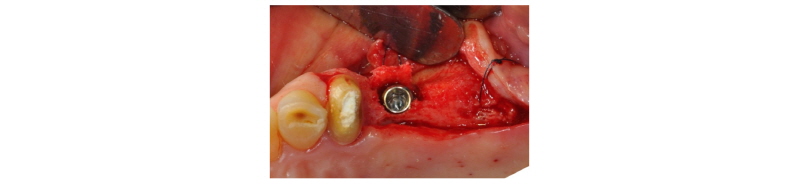

57세의 여성 환자로 기존 브릿지 보철 수복물(#24-27)의 상악 좌측 제 2대구치의 심한 우식으로 인해 내원하여 해당 치아를 발거하였다(Fig. 1). 상악 좌측 제 1 소구치는 근관치료를 시행한 후 보철 수복하기로 하였고 기존 pontic 부위였던 좌측 제 2 소구치와 발거된 제 2 대구치 부위에 #25i, #27i 2개의 임플란트 식립을 통한 브릿지 보철 수복물을 계획하였다(Fig. 2). 기존 pontic으로 유지되었던 좌측 제 2 소구치 부위는 치조제의 심한 수평적 치조골 흡수를 구강 내 임상검사를 통해 확인할 수 있었다. 전층 판막 형성후 상악 좌측 제 2 소구치 부위의 치조정 폭경은 약 2 mm 정도로 측정되었다(Fig. 3, 4). 치조골의 구개측에 약 1 mm의 치조골이 남도록 high speed carbide round bur를 이용하여 치조정에 horizontal intraosseous groove를 형성하였고 협측골의 근심, 원심측에 2개의 vertical intraosseous groove를 형성하였다(Fig. 5). Chisel과 ridge spreader drill (RS kit, Dentium, Korea)을 이용하여 점차적으로 협측 골판을 구개측으로부터 분리시켰다(Fig. 6). Osteotome을 이용, 식립 깊이까지 적용하여 임플란트 식립 부위를 형성하였고 Ø4.3 × 10 mm (Implantium, Dentium, Korea) 임플란트를 식립하였다(Fig. 7). 발치 후 치유된 상악 좌측 제 2 대구치 부위는 상악동 거상술(수직 접근법)을 시행, 골이식을 한 후 4.8 × 10 mm (Implantium, Dentium, Korea)를 식립하였다(Fig. 8). 이후 이종골 이식재(Bio-Oss®, Geistlich, Switzerland)를 식립된 임플란트와 협,구개 측 치조골판 사이의 gap과 협측골판 상방에 적용하고 흡수성 교원질 차폐막(Bio-Gide®, Geistlich, Switzerland)로 피개한 다음 감장절개를 통해 장력없이 봉합하였다(Fig. 9-11). 이후 구강 내 검사 및 방사선 검사를 통해 수술부위 치유상태를 확인하였고 특이한 임상적 소견없이 정상적으로 잘 치유되었다(Fig. 12). 약 3개월 10일 정도의 치유기간 후 이차수술을 시행하였다(Fig. 13). 판막 거상 후 치조제 분할술을 시행하였던 상악 좌측 제 2 소구치 부위에 잘 형성된 신생 골양조직이 관찰되었다(Fig. 14). 상악 좌측 제 2 소구치 부위와 상악 좌측 제 2 구치 부위에 치유지대주를 장착하였고 상악 좌측 제 1 대구치 부위에 추가적으로 임플란트를 1회법으로 식립하였다(Fig. 15). 이차수술 이후 정상적으로 치유가 진행되어 약 2개월 후 최종 보철물 수복을 하였다(Fig. 16, 17). 약 1년 정도의 follow-up시 구강 내 검사와 방사선 검사를 통해서 임플란트 주위 연조직과 변연골이 잘 유지되고 있음을 확인하였다(Fig. 18).

Fig. 3. Clinical view. Pre-op. |